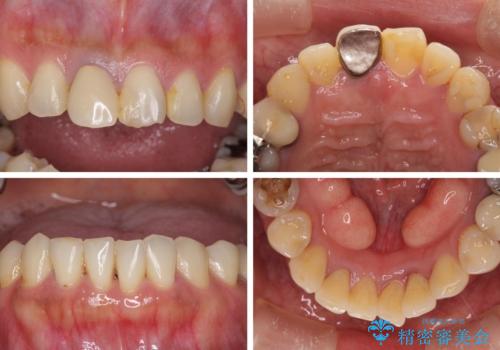

気になる部分を全て治療 総合歯科治療で口腔内環境改善

- 右下の欠損部の治療を希望して来院された患者様です。

部分矯正を行った後にインプラント埋入と手前の歯の根管治療を行い、その後補綴治療を行うこととしました。

治療途中より、上の歯や反対側の銀歯、上顎前歯の色合いや下顎前歯のデコボコが気になってきたため、全てを治療することとしました。

仕事が多忙な方で、来院間隔が開いてしまうことが多く、治療期間はかかりましたが、来院回数は最小限で終えることができました。